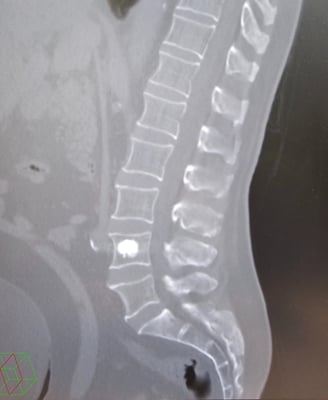

Vertebroplastias e Cifoplastias

A vertebroplastia e a cifoplastia são procedimentos minimamente invasivos utilizados para tratar fraturas por compressão na coluna vertebral. Na vertebroplastia, o médico injeta um cimento especial diretamente no corpo vertebral fraturado, fortalecendo-o e aliviando a dor. Já na cifoplastia, é inserido um balão na vértebra fraturada e, em seguida, o cimento é injetado no espaço criado, restabelecendo a altura vertebral e aliviando a dor. Ambos os procedimentos são realizados sob anestesia geral e levam cerca de 2 horas para serem concluídos. Após a cirurgia, os pacientes podem experimentar alívio imediato da dor e retomar gradualmente suas atividades normais. No entanto, é importante seguir as orientações médicas para garantir uma recuperação adequada.